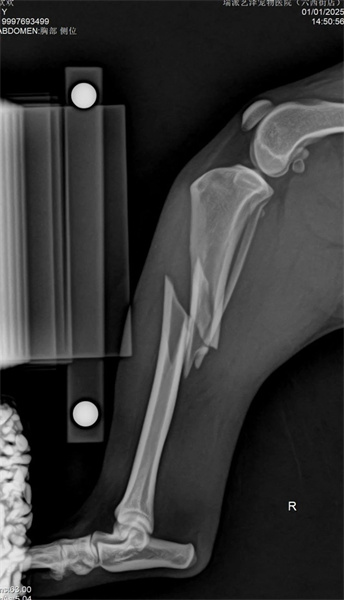

動物基本資料:鄉村犬,7公斤1歲,骨折原因:車禍

右脛骨幹粉碎性骨折(閉合性)

脛骨採用內側MIPO手術入路,盡可能保護軟組織,並以髓內釘及橋接骨板固定。